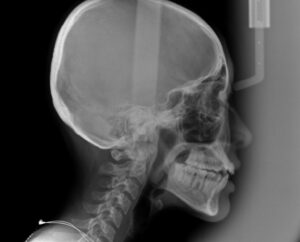

治療に先立ち精密検査用のレントゲン

セファロを撮影

最新のお口のスキャナー

トリウスで歯並びをスキャン

この資料を参考に

歯科医が分析して治療を計画

歯並びガタガタの歯の重なりは

10ミリ未満のため

今回は非抜歯でGo‼️

(10ミリ以上の歯の重なりがあれば

小臼歯を抜歯して矯正)